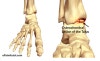

거골의 박리성 골연골염(Osteochondral lesion of talus) : 아무것도 하지 않는데 발목의 안쪽이 갑자기 아파지고 잠시 후에 자연히 사라져요. 최근에 빈도가 높아져 좀처럼 통증이 가시지 않게 되었어요

거골 활차의 골연골장애입니다.

종전에는 한 번의 외상으로 일어나는 것을 골연골골절, 분명한 외상의 기왕력 없이 일어나는 것을 박리성 골연골염이라고 해왔지만 분명하게 구별할 수 있는 것은 소수이며, 별로 구별할 필요도 없기 때문에 골연골병변이라고 총칭되고 있습니다.

1. 외측 병변(40%) : 90% 이상 외상과 관련, dorsiflexion, tibia의 internal rotation이 함께 일어나는 강한 inversion

2. 내측 병변(60%) : Plantar flexion, tibia의 external rotation이 함께 일어나는 강한 inversion